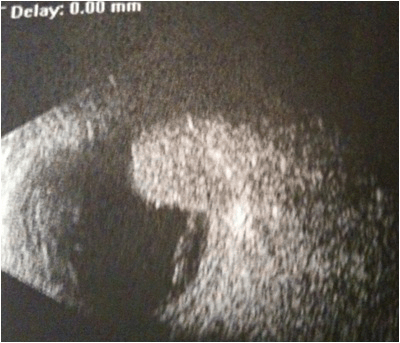

A 63-year-old man presented with blurred vision and a progressive loss of visual acuity for approximately two weeks. Medical history was remarkable for infiltrating breast carcinoma with negative complete work-up, for which he has had mastectomy, radiation therapy and chemotherapy in 2009. Ophthalmic examination showed exophthalmos of the right eye without ptosis. Ocular motility was normal. Best corrected visual acuity was (BCVA) 3/10 on the right eye and 7/10 on the left eye. Anterior segment examination was normal on both eyes with no dense cataracts observed. Fundoscopy under pupil dilatation in the right eye revealed an ill-defined choroidal mass in the upper temporal arcade, impinging on the macula and surrounding the papilla. The mass was associated with pigment epithelium impairment and normal optic discs, without macular edema. Fundoscopy in the left eye did not reveal any tumor. Standardized B-scan ultrasonography of the right eye revealed a posterior, hyperechogenic tumor of the choroid with secondary retinal detachment associated with choroidal thickening (Figure 1). Indocyanine green chorioangiography (ICG) was unremarkable in the left eye, but revealed a tumor in the right eye (Figures 2, 3). Magnetic resonance imaging (MRI) revealed a right ocular expansive lesion with non-circumferential posterior choroidal thickening (Figure 4).

Figure 1: Standardized B-scan ultrasonography of the right eye showing a posterior, hyperechogenic tumor of the choroid with secondary retinal detachment associated with choroidal thickening.